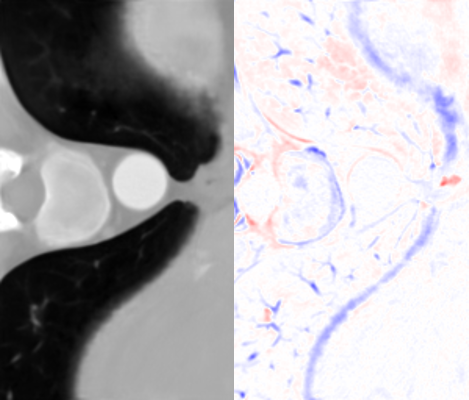

Figure 7: Visual comparisons of different methods against SAINT. The difference maps are provided to the right of the results for better visualization. Images are best viewed when magnified.

In this section, we evaluate the performance of our method and other SISR approaches. Quantitative comparisons are presented in Table 2. MDCSRN uses a DenseNet structure with batch normalization, which has been shown to adversely affect performance in super-resolution tasks [17, 27]. Furthermore, inference with 3D patches lead to observable artifacts where the patches are stitched together, as shown in the mDCSRN results in Fig. 7.

For liver, colon and hepatic vessels datasets, SAINT drastically outperforms the competing methods; however, the increase in performance is less significant with the kidney dataset. Generalizing over unseen dataset is a challenging problem for all data-driven methods, as factors such as acquisition machines, acquisition parameters, etc. subtly change the data distribution. Furthermore, quantitative measurements such as PSNR and SSIM do not always measure image quality well.

We visually inspect the results and find that SAINT generates richer detail when compared to other methods. It is evident in Fig. 7 that there is a least amount of structural artifacts remaining in the different images produced by SAINT. For more discussion on SAINT’s advantage in resolving the memory bottleneck and more slice interpolation results, please refer to the supplemental material section.